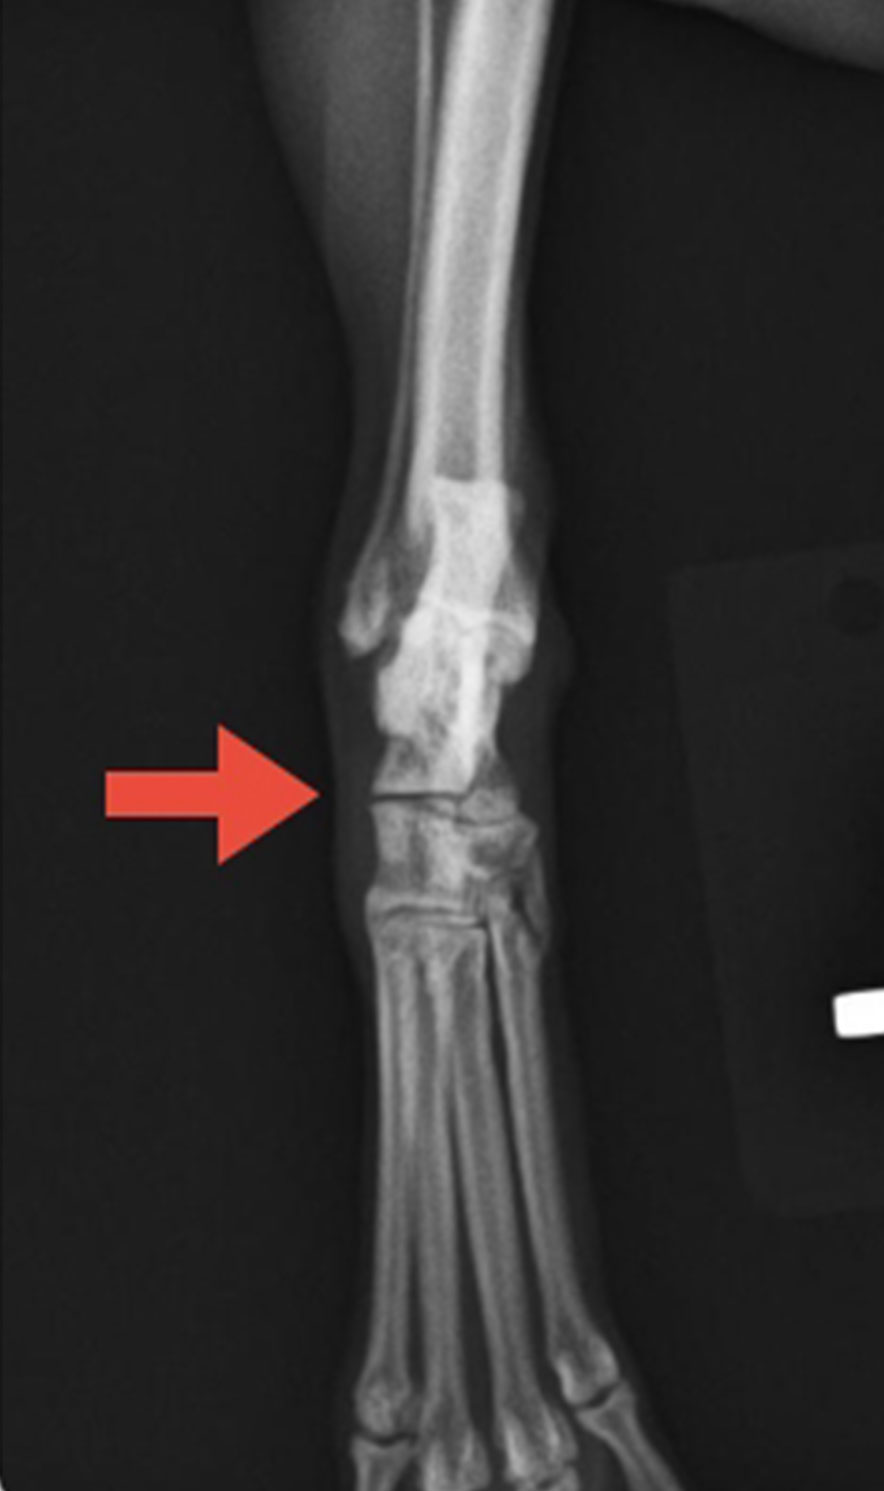

犬種:ポメラニアン、年齢:10ヶ月齢、体重:2.2kg、性別:オス

椅子から落下し右前腕の橈骨と尺骨を骨折した症例です。

術前計画で骨の大きさ、入れるプレート・スクリューを確認します。

手術は観血的に骨の変位を整復し、プレートとスクリューで内固定しております。この症例ではSynthesのプレート(LCP1.5)とスクリュー(コーテックスクリューとロッキングスクリュー)をハイブリットで使用しております。

術前レントゲン検査 術前計画 術後レントゲン検査

側面像 側面像 側面像

頭尾側像 頭尾側像 頭尾側像